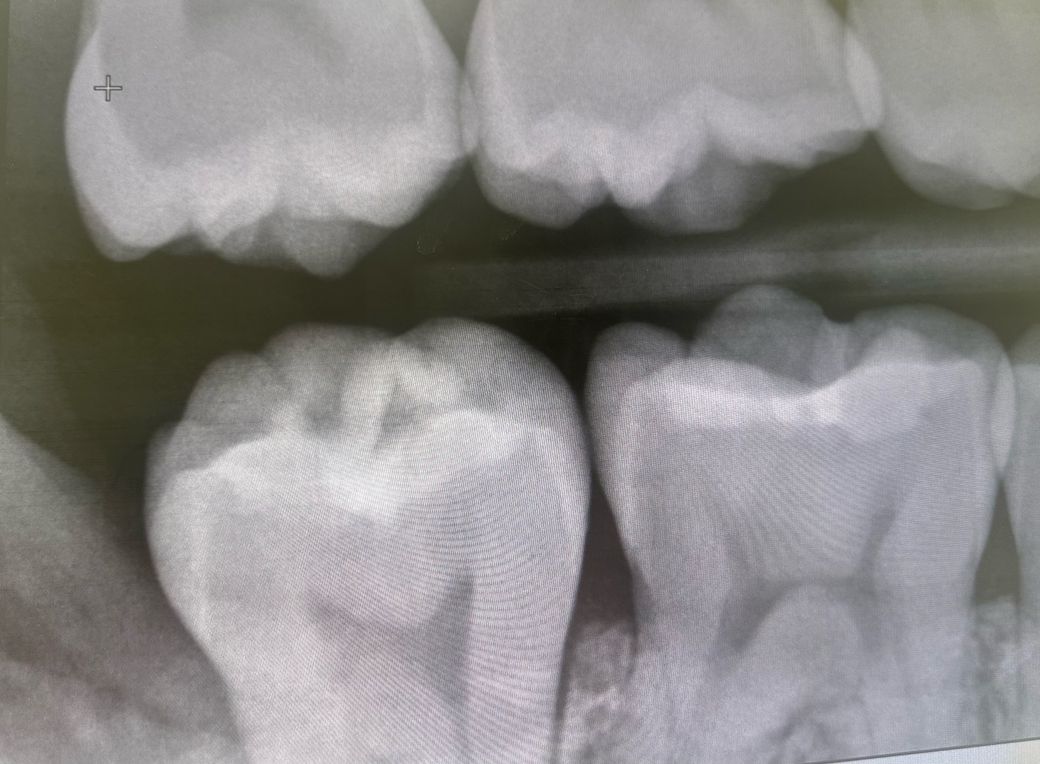

차례대로 사랑니발치전, 발치후, 가까이서 찍은 엑스레이입니다…

• 2번 째 사진